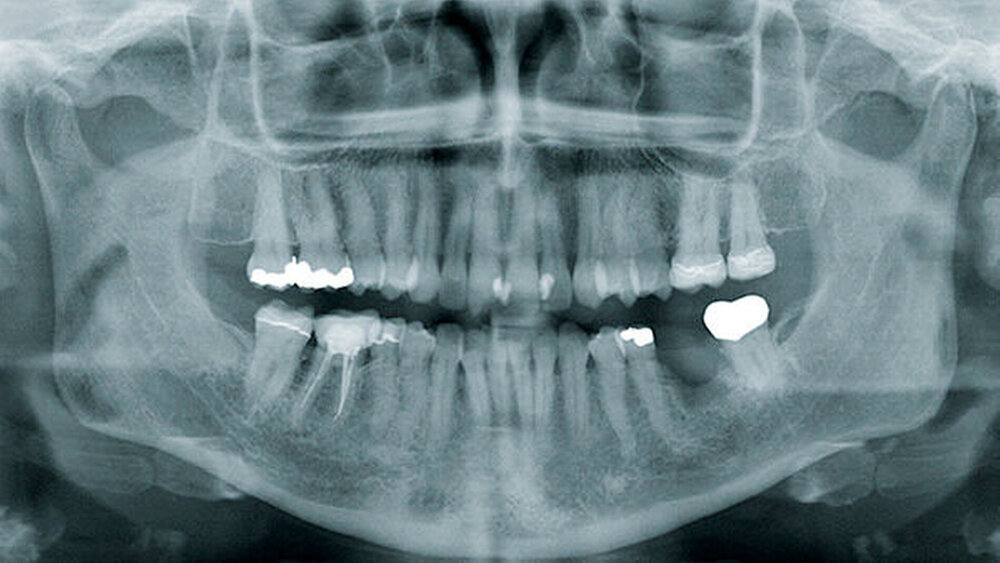

Die akute (infektiöse) OM geht nach vier Wochen per definitionem in eine sekundär chronische OM über (Abbildungen 1 und 2) [Marx, 1991] und beschreibt daher eigentlich die gleiche Entität zu unterschiedlichen Zeitpunkten und zu unterschiedlichen Stadien.

Die konventionelle Panoramaschichtaufnahme (PSA) hat als Ausgangsuntersuchung weiterhin einen großen klinischen Stellenwert (Abbildungen 1 und 3). Sie gibt einen ersten Überblick über Knochenstruktur und Zahnstatus. Ihre Aussagekraft ist jedoch aufgrund von Überlagerungseffekten limitiert [Strobel et al., 2012]. Darüber hinaus ist sie nicht sehr sensitiv, da erst ab einem Knochensubstanzverlust von etwa 30 bis 50 Prozent eine Osteolyse im Röntgenbild erkennbar ist.